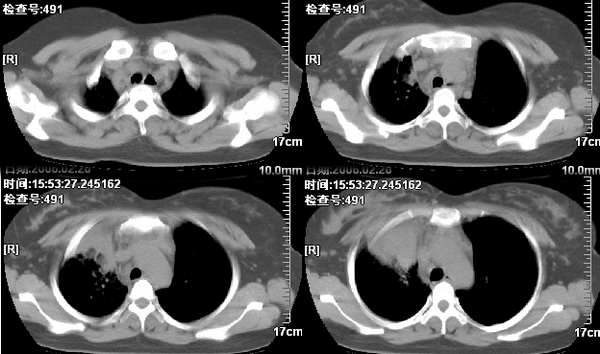

女,28岁咳嗽无痰偶有低烧,化验:白细胞1万零7,血沉正常

有没有做增强?可以把增强的片子上传吗?肺窗呢?(纵隔内好象有一淋巴结影)

右肺上叶前段与中叶见较大团块影。边界较清晰,纵隔隆突前淋巴结增大。考虑1肺部间叶组织肿瘤可能。2感染性病变

我觉得不要把患者年龄作为轻易排除肺癌的依据,病变呈大块状软组织密度,右肺中叶支气管可见中断,右侧肺门增大,要高度警惕肺癌,支气管镜应该能够给出正确的诊断。间质来源的恶性肿瘤尽管可以考虑到,但是从发病率上来说不首先考虑。

纵隔内淋巴结肿大不是非常明显。但肺部征象明显。还是第一次见到。学习了!!!!!

补充病例结果是:肺间变大t细胞淋巴瘤. 非霍奇金淋巴瘤(间变大t细胞性)iv期bipi 2分

右肺中下叶切除